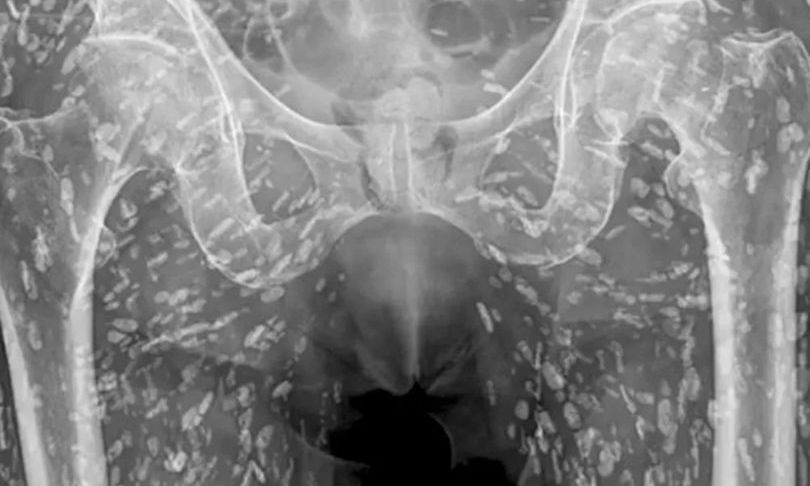

PRONEWS.GR / Υγεία Άνδρας γέμισε «αυγά» στη λεκάνη του από κακοψημένο χοιρινό – Δείτε την ακτινογραφία του (φώτο) 23.01.2025 | 09:39